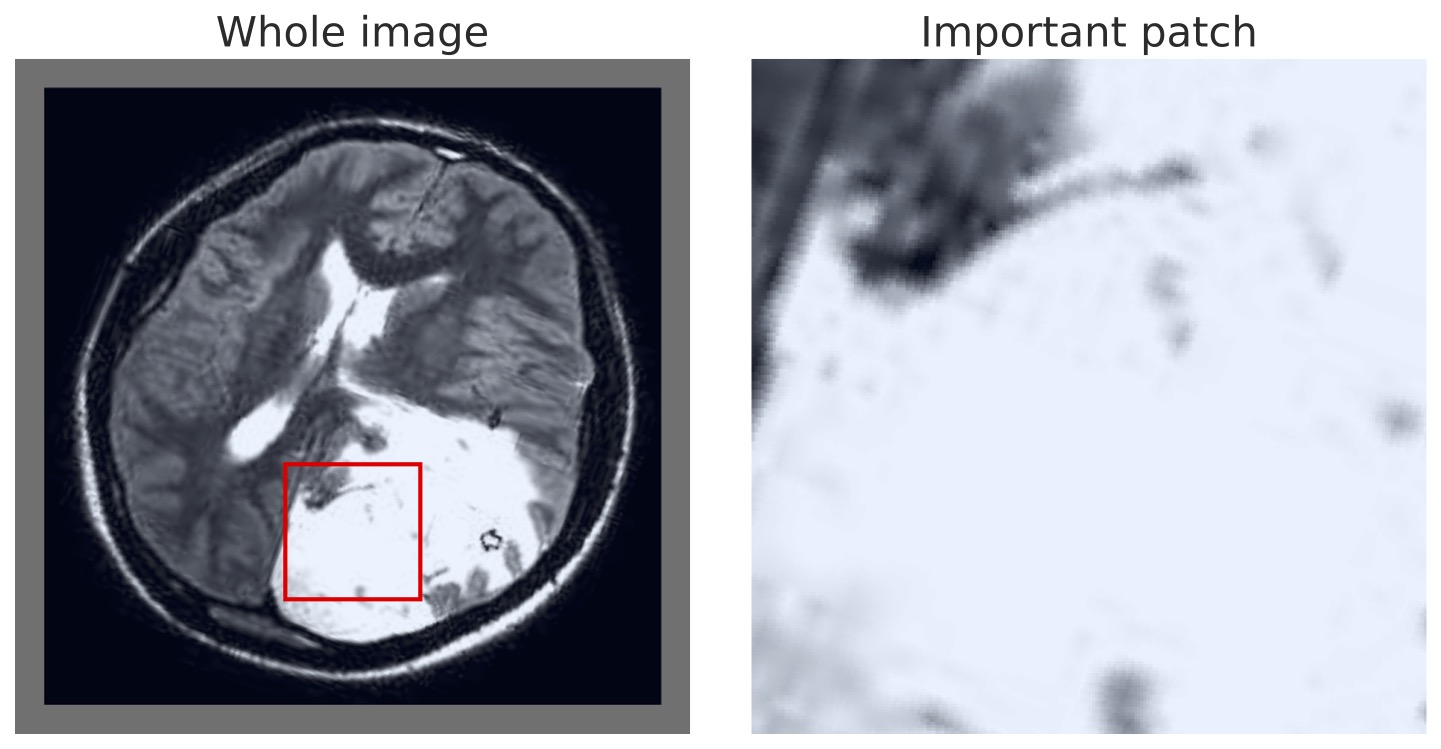

A further benefit of our approach is that the concept vectors can be used to gain an interpretable component about what the model is learning to look for. We can do this by showing example patches that correspond to the ’th concept vector activating and having the maximal response, i.e., making the classification determination. We provide an example for the first five concept classes on the BTMD dataset in Figure 4 and the RSNA-SMBC dataset in Figure 5. In both cases, the row corresponds to a concept, and 25 columns show 25 winning exemplars.

The BTMD dataset has considerably more visual variation in the images, making them more challenging to inspect as non-medical experts, but visual themes are generally discernible across each row in Figure 4. We note that there is no mechanism to force one concept vector to suppress other concept vectors for similar activations, and so we see some cross-pollination between the concept vectors. The RSNA dataset has less visual asperity, and visual patterns are more clearly observed in the rows of Figure 5.

Finally, we can also visualize the results of our MIL model in the same manner as prior approaches, highlighting either the most positive, or all positive, regions to allow interpretable inspection and verification. This is demonstrated in Figure 6 using the BTMD dataset, in which tumors are recognizable to non-medical experts. The appendix has additional random samples from the other dataset.

In Figures 7 and 8, we display more representative patches selects that correspond highly to a given concept vector (one concept per row), highlighting our our method automatically learns sub-regions of the larger image space.

In Figure 9 we show multiple BTMD images randomly selected and the maximal positive detection region from each image. In each case it is clear that the model successfully focuses on the malignant portions.